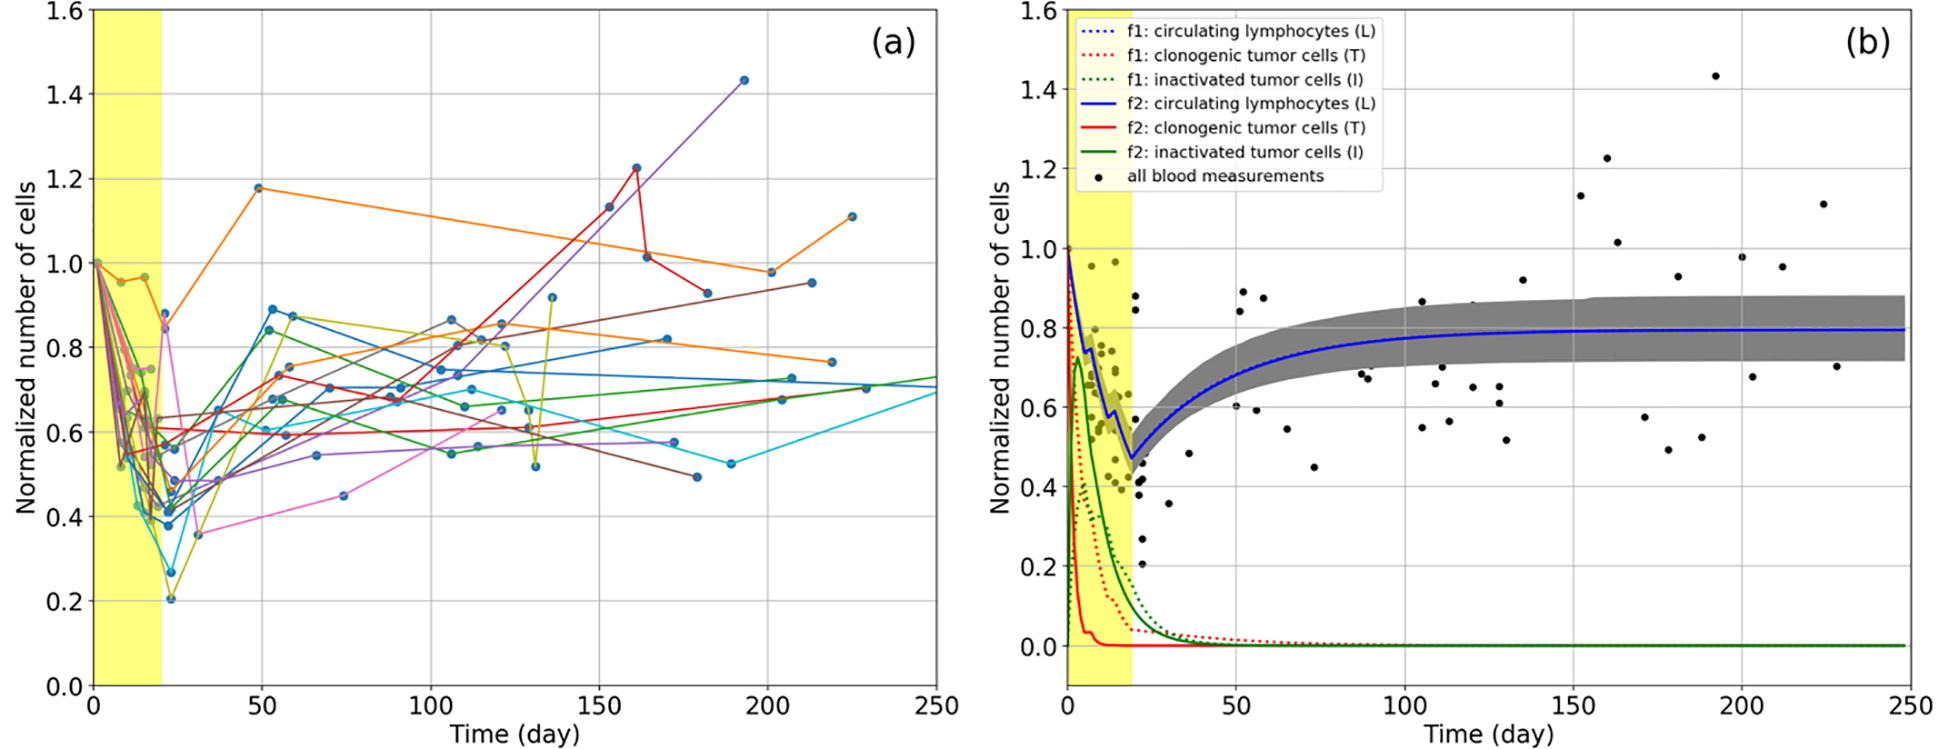

The impact of radiation therapy on the immune system has recently gained attention particularly when delivered in combination with immunotherapy. However, it is unclear how different treatment fractionation regimens influence the interaction between the immune system and radiation. The goal of this work was to develop a mathematical model that quantifies both the immune stimulating as well as the immunosuppressive effects of radiotherapy and simulates the effects of different fractionation regimens based on patient data.

The framework describes the temporal evolution of tumor cells, lymphocytes, and inactivated dying tumor cells releasing antigens during radiation therapy, specifically modeling how recruited lymphocytes inhibit tumor progression. The parameters of the model were partly taken from the literature and in part extracted from blood samples (circulating lymphocytes: CLs) collected from hepatocellular carcinoma patients undergoing radiotherapy and their outcomes. The dose volume histograms to circulating lymphocytes were calculated with a probability-based model.

Based on the fitted parameters, the model enabled a study into the depletion and recovery of CLs in patients as a function of fractionation regimen. Our results quantify the ability of short fractionation regimens to lead to shorter periods of lymphocyte depletion and predict faster recovery after the end of treatment. The model shows that treatment breaks between fractions can prolong the period of lymphocyte depletion and should be avoided.